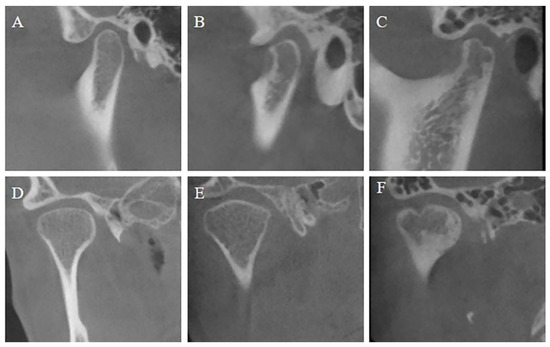

2.2. Assessment of Condyle Morphology with CBCT Images